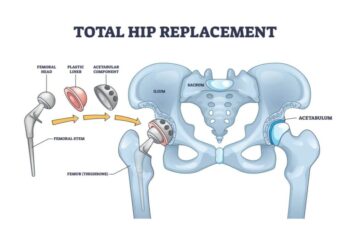

Total Hip Replacement In Nagpur – Advanced Treatment for Hip Pain Total Hip Replacement In Nagpur at Asian Institute Of Advanced Surgeries,By Dr. Abhishek Bhalotia, practicing Total hip replacement...